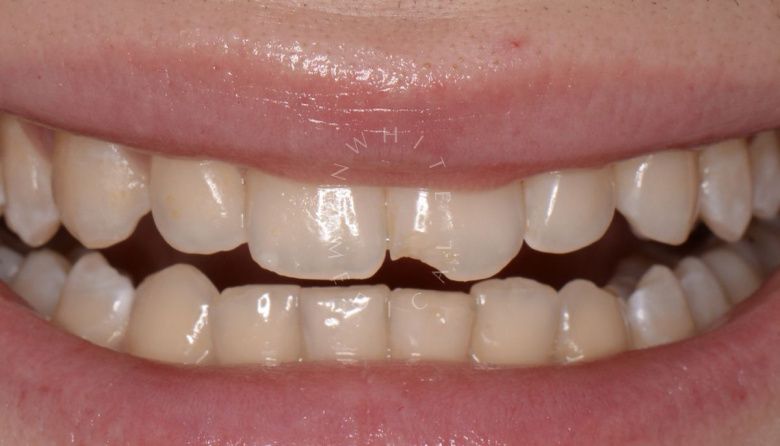

Художественная реставрация формы зубов

Стоматология Москва лучшие клиники. Художественная реставрация формы зубов - после процедуры